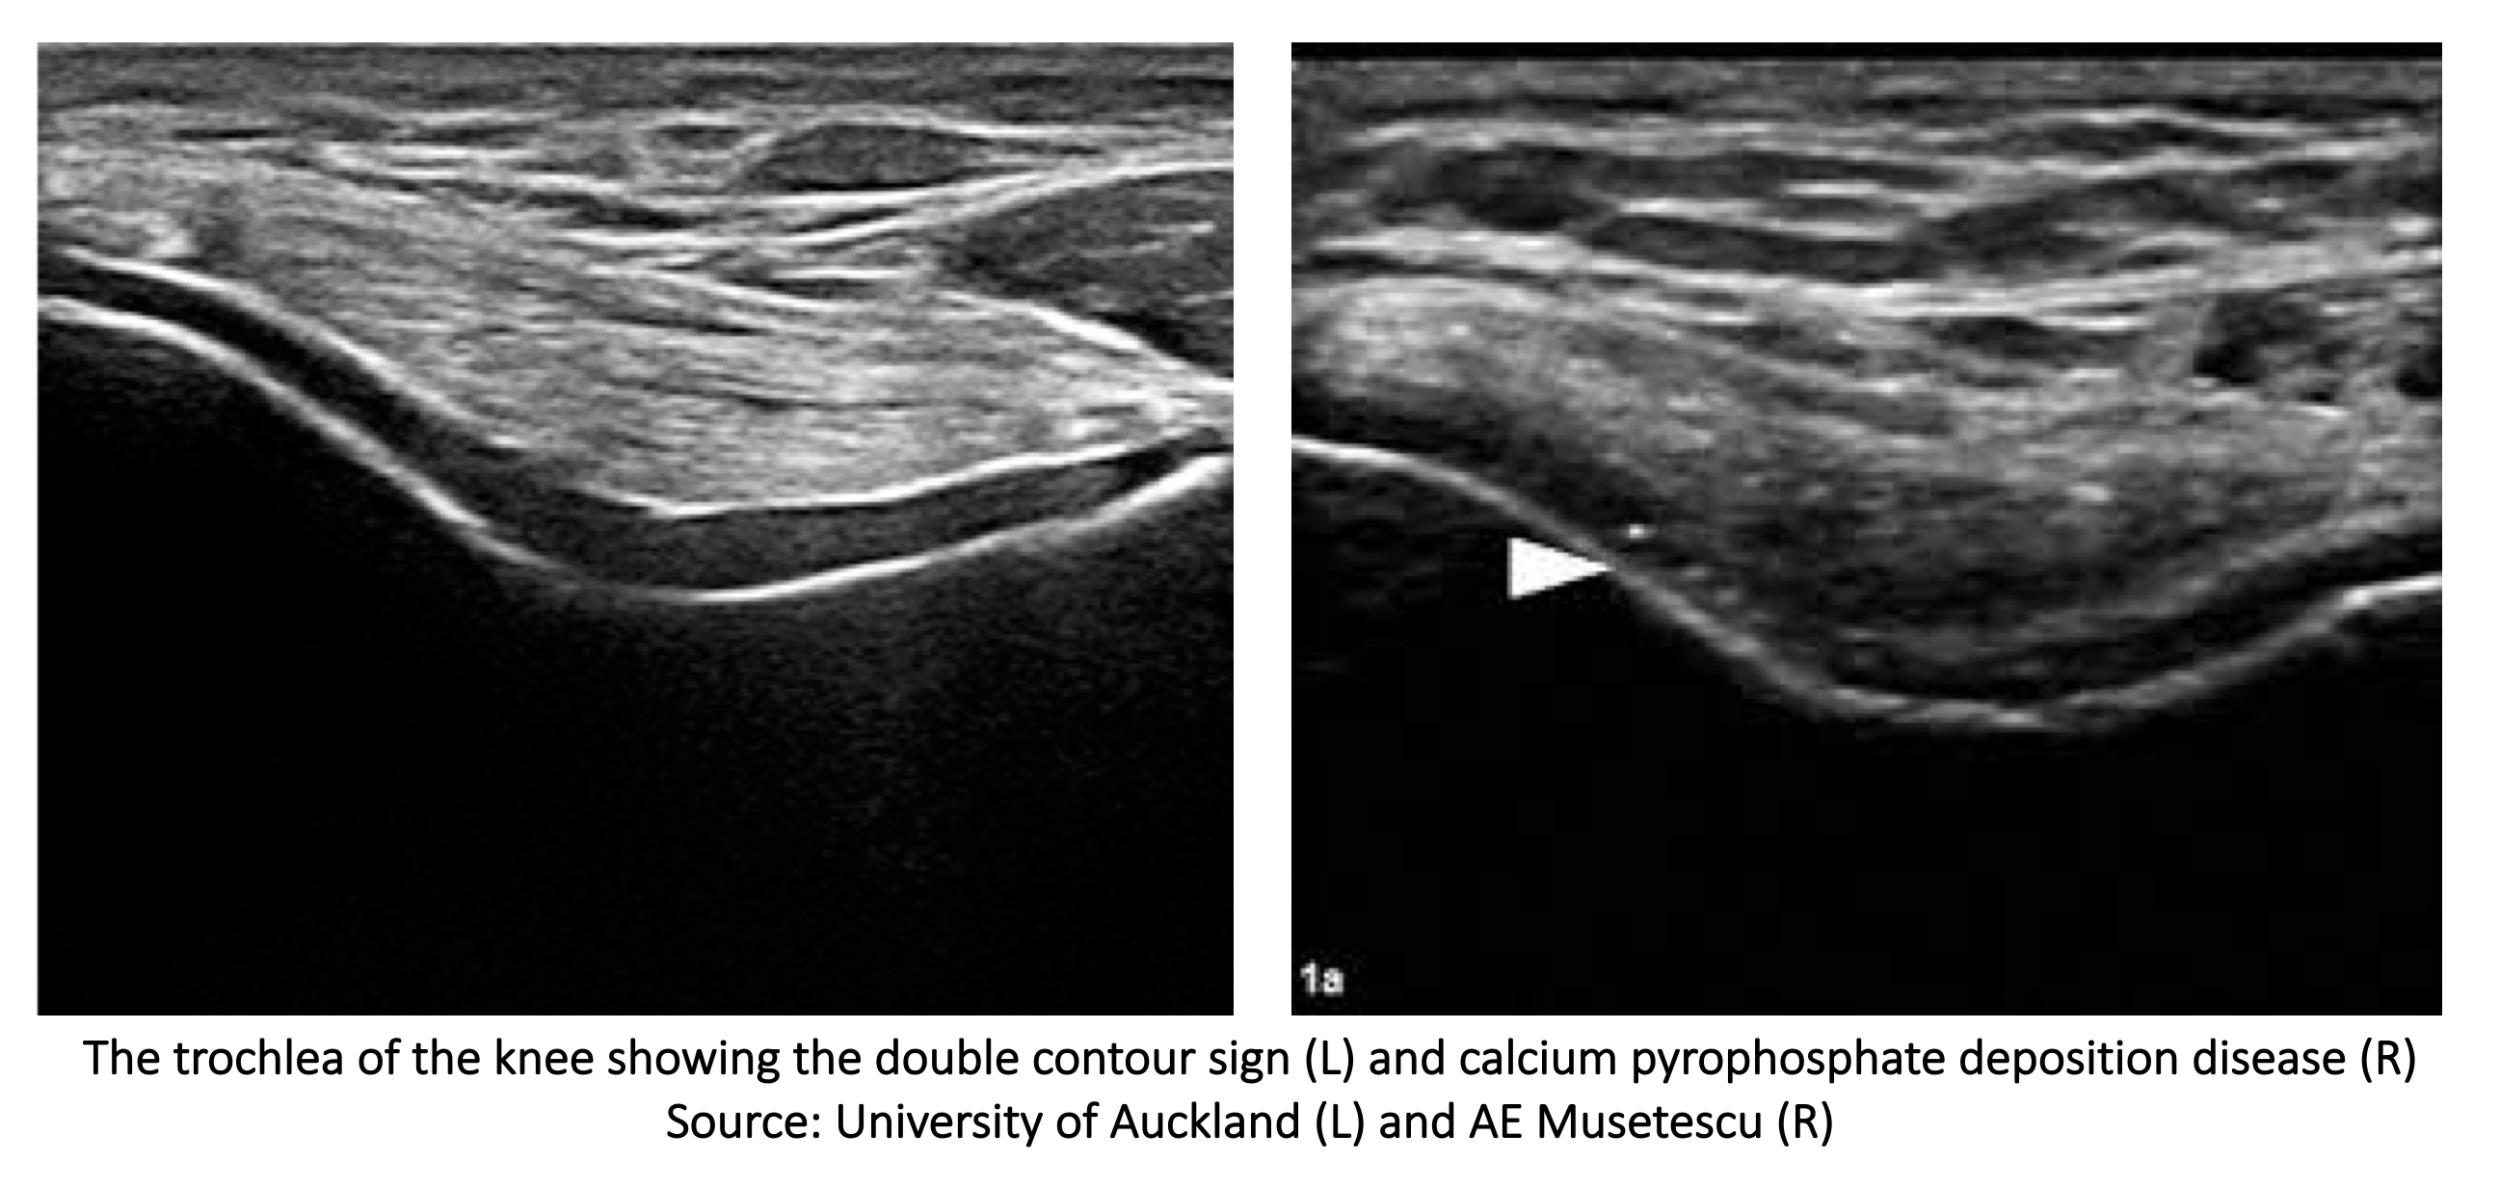

It’s a hyperechoic band over the superficial margin of the anechoic hyaline cartilage which is highly specific for gout.

Assuming that you’re doing a great job with scanning the hyaline cartilage in normal joints perfectly perpendicular: leading to a cartilage interface artifact. This normal hyperechoic superficial margin of hyaline cartilage is thinner than the double contour sign and does not persist with dynamic movements because the double contour sign is not dependent on the angle of the US beam (not anisotropy related).

The double contour sign should be distinguished from the cartilage appearance in calcium pyrophosphate deposition disease, where a hyperechoic band from calcium deposits is seen within the middle of the hyaline cartilage, not at the margin.